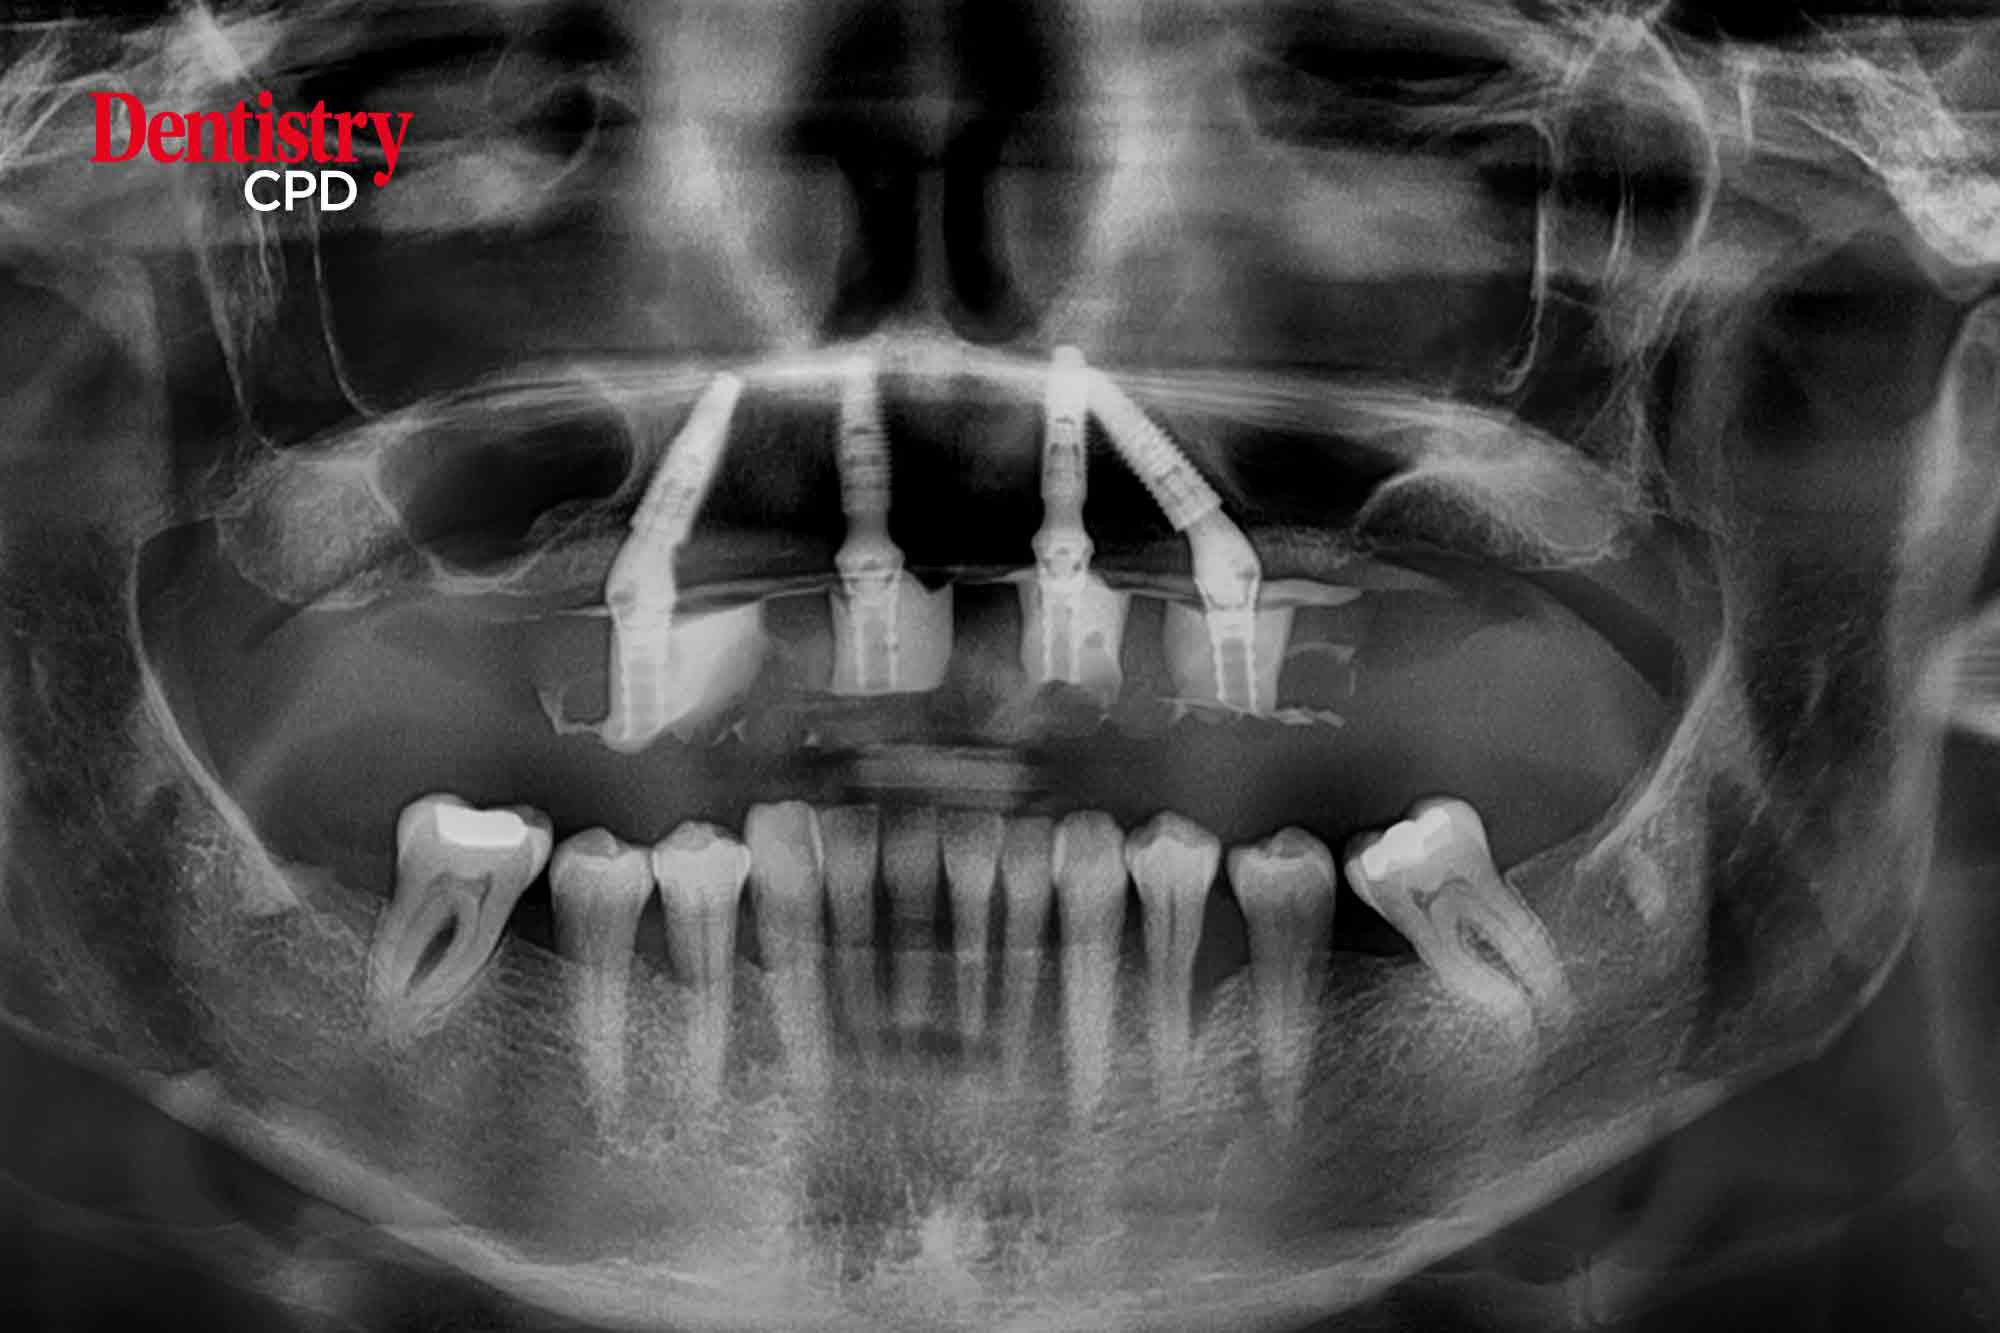

Ferhan Ahmed shares a case where he provided planning and surgical support to colleague Melanie Edwards for an implant case.

To show how correct treatment planning including involvement of the patient and extended dental team can deliver a successful outcome for implant cases.